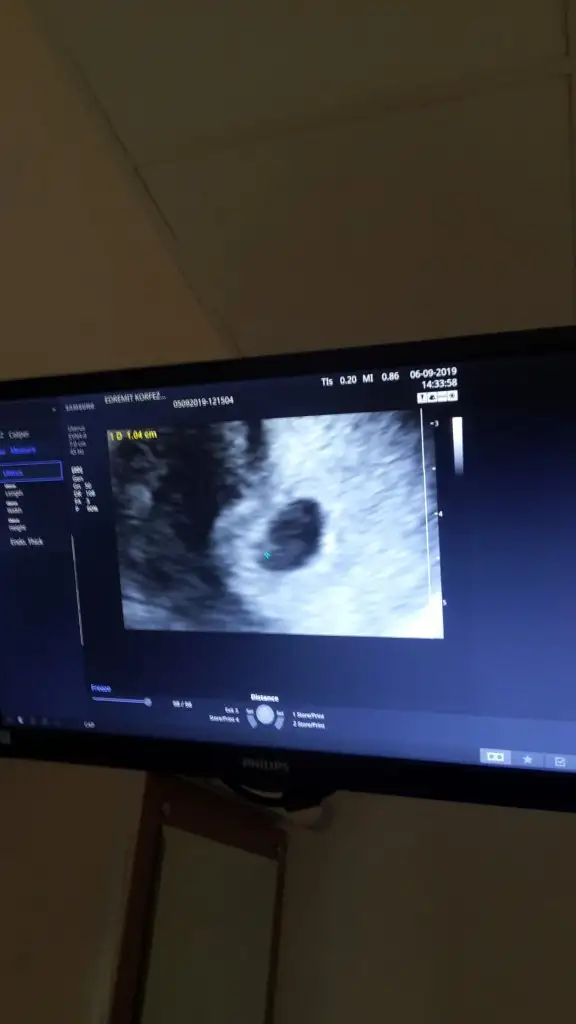

Nacizane tavsiyem kürtaj geçmişiniz varmış lütfen ilk fırsatta doktora gidin.Ben de öyle 7 haftalıkken kürtaj olmak zorunda kaldım günüm geçti ara ara leke geliyor erken olduğu için doktora da gitmek istemiyorum inş bi sıkıntı olmaz